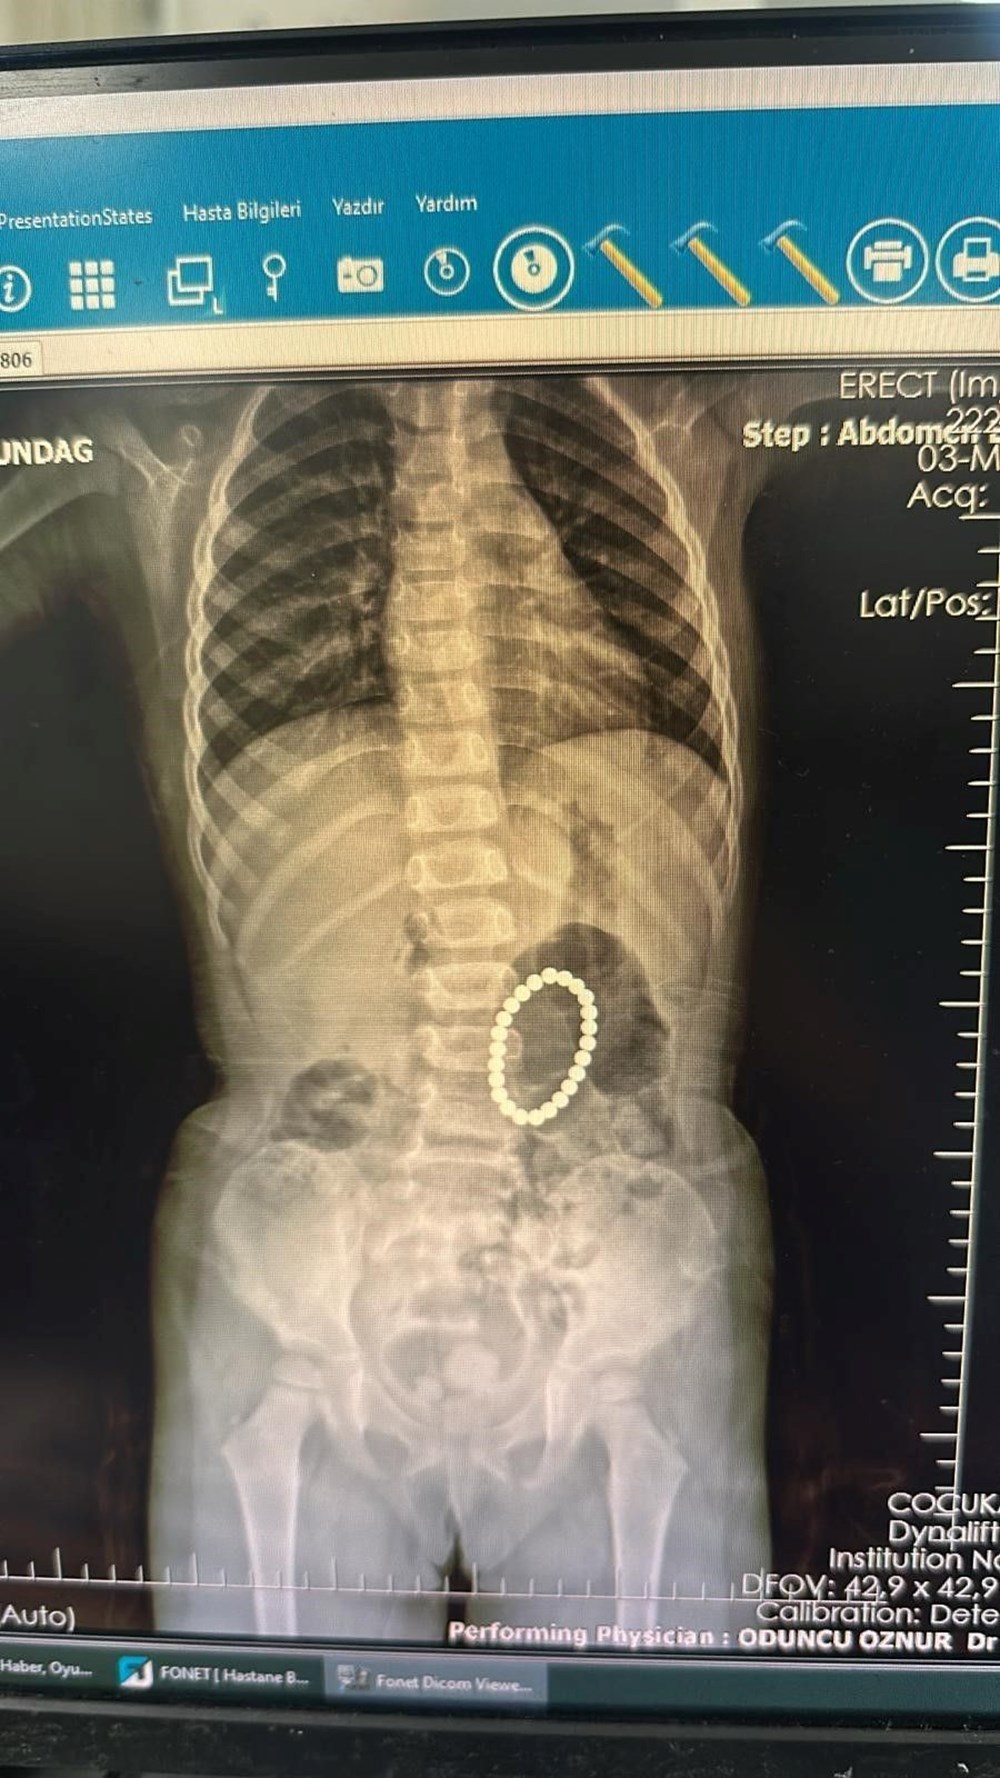

Batman’a getirilen Rumeysa Altundağ’ı tetkik eden Batman Eğitim ve Araştırma Hastanesi Çocuk Cerrahisi Doktoru Selim Özkaya, sonrasında hastaya endoskopi uyguladı. Uygulanan endoskopide küçük kızın bağırsaklarında ve midesinde bileklik şeklinde yabancı unsurların olduğu tespit edildi. Cerrahi operasyona alınan Rumeysa Altundağ’ın bağırsakları ve midesinden 24 adet renkli oyuncak mıknatısı çıkarıldı.

İlk defa bu şekilde bir durum ile karşılaştıklarını ifade eden doktor, yapılan operasyonun ardından başarılı bir şekilde tamamlandığını aktardı. Mıknatısların bağırsaklarda kısmi yırtılmalara neden olduğunu belirten Dr. Özkaya, “Hastamız 4 yaşında kız çocuğu. Şiddetli karın ağrısı sebebiyle Şırnak’taki devlet hastanemize başvurmuş, yapılan incelemelerinde yabancı cisim yuttuğu saptanmış. Bunun üzerine endoskopi yapılması için hastanemizin Gastroenteroloji bölümüne yönlendirildi. Endoskopi esnasında saptanan yabancı cisimlerin renkli mıknatıslar olduğu, yarısının da midede görünmediği anlaşıldı. Hastamız 24 tane renkli küçük mıknatıs yutmuştu. Endoskopi sürecinden sonra hastamıza ameliyat planladık. Yaptığımız ameliyatta da farklı zamanda yutulan mıknatısların yarısının midede yarısının bağırsaklarda olduğu ve bunların birbirine yapışarak bağırsak bölgelerinde delinmelere yol açtığı belirlendi. Bu bölgeleri onardık. Hastamız ameliyattan sonra beslenmesine de başladı, herhangi bir sorunu yok, taburcu etmeyi düşünüyoruz” şeklinde konuştu.

Çıkarılan mıknatısların yaklaşık 1 yıl önce yutulduğuna dikkat çeken Dr Özkaya, “Bu mıknatısların bir yıl kadar bir süredir yuttuğunu düşünüyoruz. Çünkü bu mıknatısların artık renkleri de değişmiş durumda ve paslanmış durumda. O yüzden de bir yıldır aralıklı karın ağrısı çekiyormuş. Bunlar renkli renkli ve kuvvetli mıknatıslar” ifadelerini kullandı.